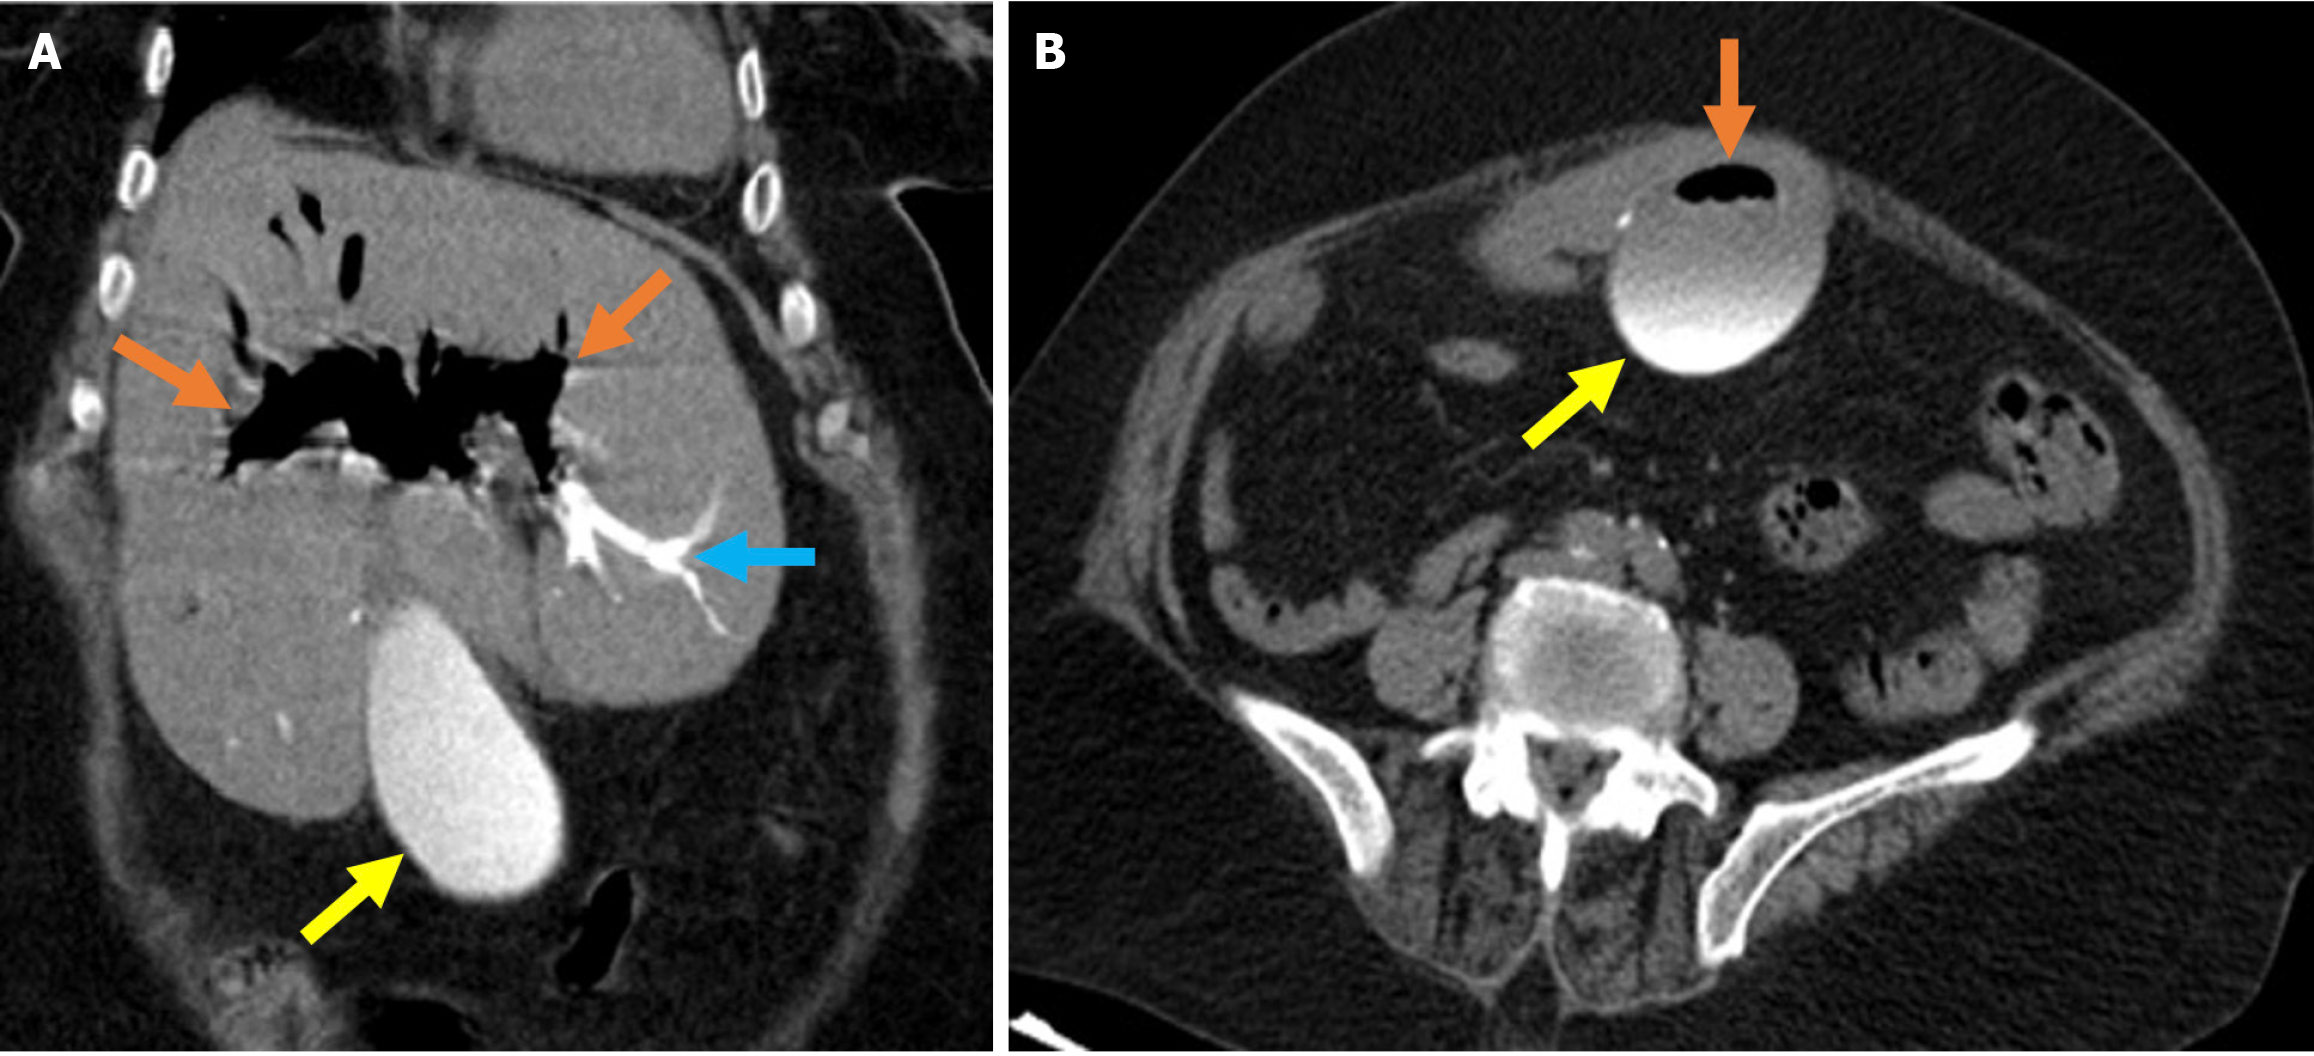

The revised Atlanta classification recognizes two primary forms of acute pancreatitis: NP and interstitial edematous pancreatitis (IEP). NP tends to follow a more severe clinical course with higher rates of infection, organ failure, and mortality. Imaging reveals hypoperfused or non-enhancing areas indicating NP or peripancreatic necrosis. Early collections (within 4 weeks) are referred to as acute necrotic collections. Once encapsulated after 4 weeks, they are known as walled-off necrosis (Figure 3)[23]. IEP is characterized by a diffusely enlarged pancreas with homogeneous enhancement on CECT imaging without areas of necrosis and with peripancreatic fat stranding and fluid accumulation. Fluid collections observed within the first 4 weeks are termed acute peripancreatic fluid collections, while those persisting beyond 4 weeks are classified as pancreatic pseudocysts (Figures 4 and 5).

Figure 3

Figure 3 Necrotizing pancreatitis, acute necrotic collections, and walled-off necrosis. A and B: Contrast-enhanced axial computed tomography (CT); C: T2-weighted magnetic resonance imaging (MRI); D: Post-contrast fat-suppressed T1-weighted MRI. A 76-year-old male patient underwent endoscopic retrograde cholangiopancreatography due to choledocholithiasis. On the evening of the procedure, the patient developed acute abdominal pain that was unresponsive to analgesics. Laboratory tests revealed elevated levels of aspartate aminotransferase, alanine aminotransferase, and lipase. Within the following 24 hours, the patient’s condition deteriorated and developed into shock. Subsequently, the patient required vasopressor support and intubation. Contrast-enhanced CT (A and B) was performed due to the severe abdominal pain. The images showed a markedly enlarged pancreas with areas of non-enhancement consistent with necrotizing pancreatitis that was accompanied by peripancreatic edema (yellow arrows). Heterogeneous acute necrotic collections were also observed in the peripancreatic region (blue arrows). Two months later, an MRI was performed for follow-up. On T2-weighted images (C) a collection with a heterogeneous internal structure and defined wall that was consistent with walled-off necrosis was visualized (orange double-sided arrow). There was a significant loss of pancreatic volume due to necrosis. In the post-contrast T1-weighted fat-suppressed image (D), contrast enhancement of the wall of the collection was noted. A small remnant of pancreatic tissue with normal contrast enhancement was observed (purple arrow).